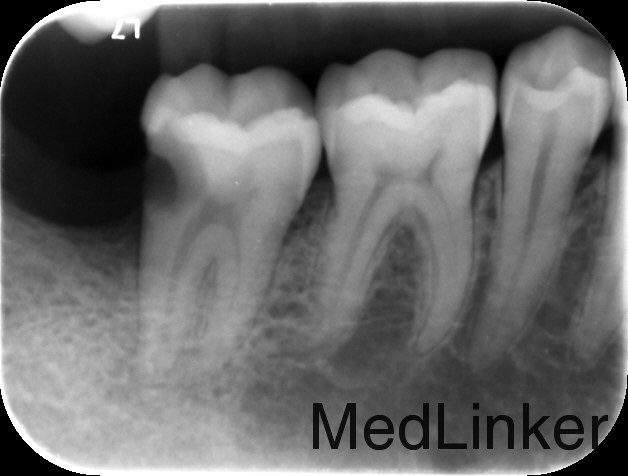

主诉:右下后牙疼痛2周 现病史:2周前自觉右下后牙疼痛,伴自发痛史,夜间疼痛史。 既往史:1年前于外院行右下阻生齿拔除术,治疗后无不适。平素体健。否认药物过敏史。

检查:47远中深龋坏,近髓,叩诊无不适,冷热测敏感,松动0度,X线片显示47远中深龋坏近髓,牙周膜影略增宽。

诊断:47牙髓炎 治疗计划:47根管治疗后冠修复。 处置:47碧蓝麻醉下,去腐,降牙合,开髓,揭髓,EDTA伴随下根管预备,冲洗,超声荡洗,干燥,激光消毒,封氢氧化钙。二次复诊:冲洗,试尖,AHplus糊剂和热牙胶充填。